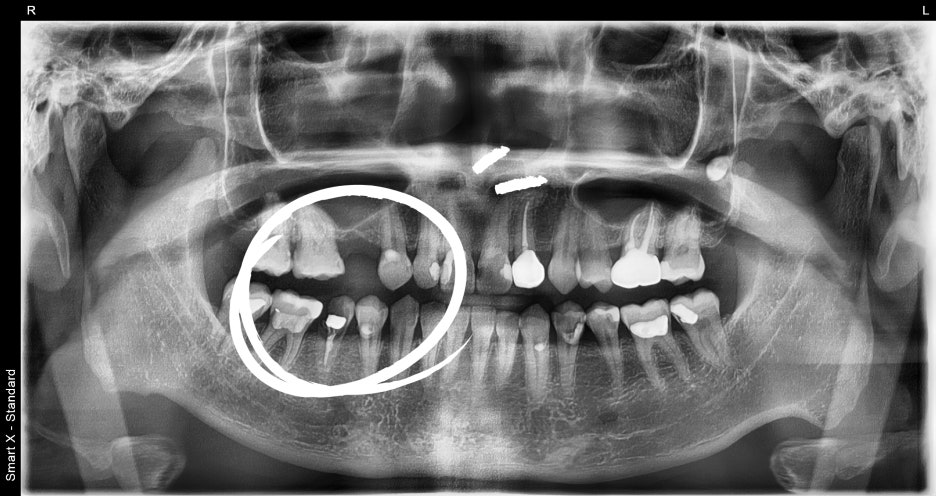

1.파노라마 촬영 결과, 오른쪽 아래 어금니는

치아가 파절되어 보존이 불가능했습니다.

발치 후 즉시 임플란트 식립이 가능한

상태로 진단되었습니다.

2.오른쪽 위 작은 어금니는 오래 전

상실된 치아였으나, 잇몸뼈의 흡수 정도가 심하지 않아

추가적인 뼈이식 없이 임플란트가 가능했습니다.